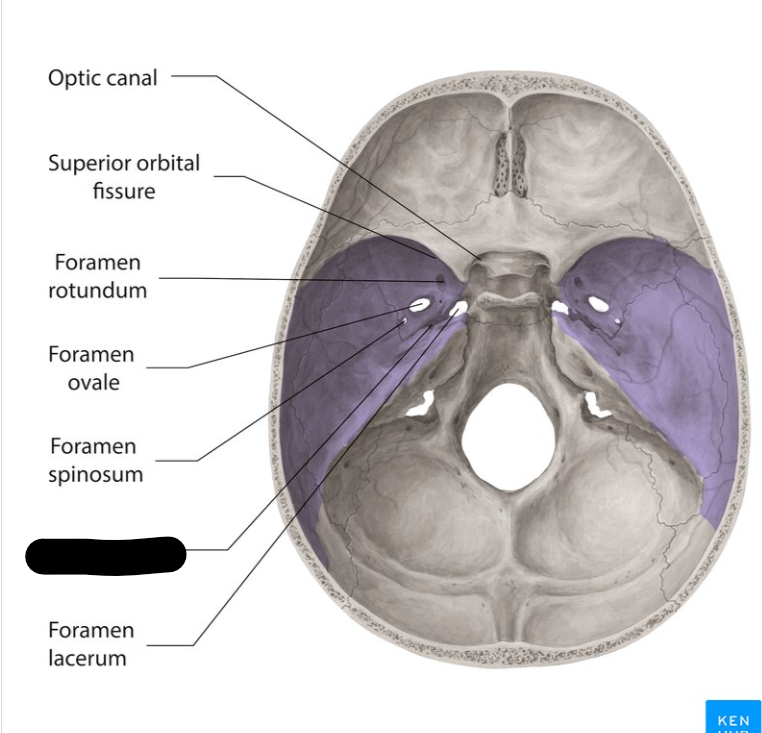

Middle cranial fossa

Foramen rotandum

Foramen ovale

Foramen lacerum

Foramen spinosum

Superior orbital fissure

Optic canal

Carotid canal